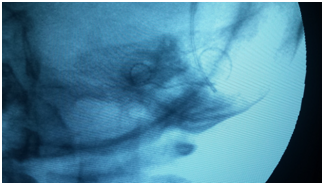

On the other hand, intraoperative radiological imaging provides confirmation of proper, intra-cochlear placement of the electrode array.9,13,17,19,21 Plain radiographs are used to evaluate electrode location, position, and presence of tip rollover. In cases of abnormal cochlear anatomy, intraoperative fluoroscopy also has been advocated as a dynamic ‘‘real-time’’ assessment of CI electrode placement.11,13

Additionally, more sophisticated imaging modalities also have been used during CI surgery, including CT and 3-D rotational x-ray, but intraoperative access to these technologies is still uncommon (Figure 3).12,13

Figure 3 Plain X ray done intra-operatively using C-arm reveling full insertion of the electrode array.